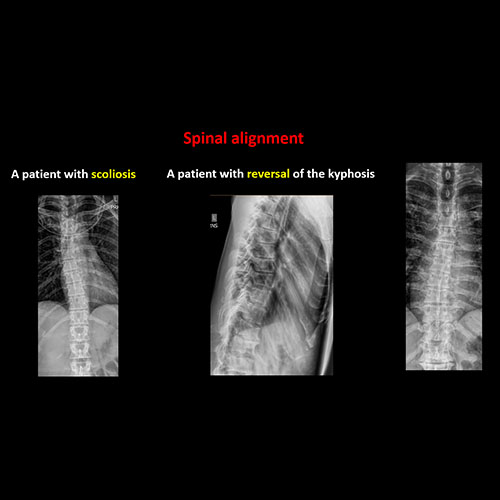

There is exaggeration, reversal, or straightening of the normal kyphosis or there is scoliosis of the thoracic spine. |

No | NA |